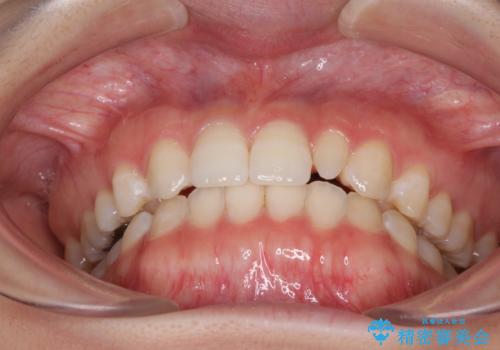

海外転居前に気になる前歯を整えたい 上下前歯の部分矯正

- 1年後に海外に転居するため、気になる前歯を矯正治療で整えたいとのことで来院された患者様です。

下顎は叢生が強かったため、奥歯までワイヤーを装着し、上顎は前歯の一部のみ気になっていたので、その部分にだけワイヤー装置を装着することとしました。

部分矯正は、適応となる症例が限定されます。

こちらの患者様は部分矯正が可能な、非常に珍しい方でしたが、部分矯正を希望される患者様の大半は、全顎矯正が必要となります。